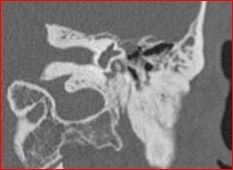

A mastoidectomy was recommended. At surgery, there was a small encephalocele protruding through a 4 mm tegmen defect (arrow, Fig. 2), with intermittent CSF leakage. The encephalocele stalk was fulgurated and the dura repaired with perichondrium and the tegmen with conchal cartilage.(Fig. 3). An abdominal fat graft was placed in the mastoid cavity. An indwelling myringotomy tube was left in place as a sentinel for continued CSF leakage.

Figure 2 Figure 2